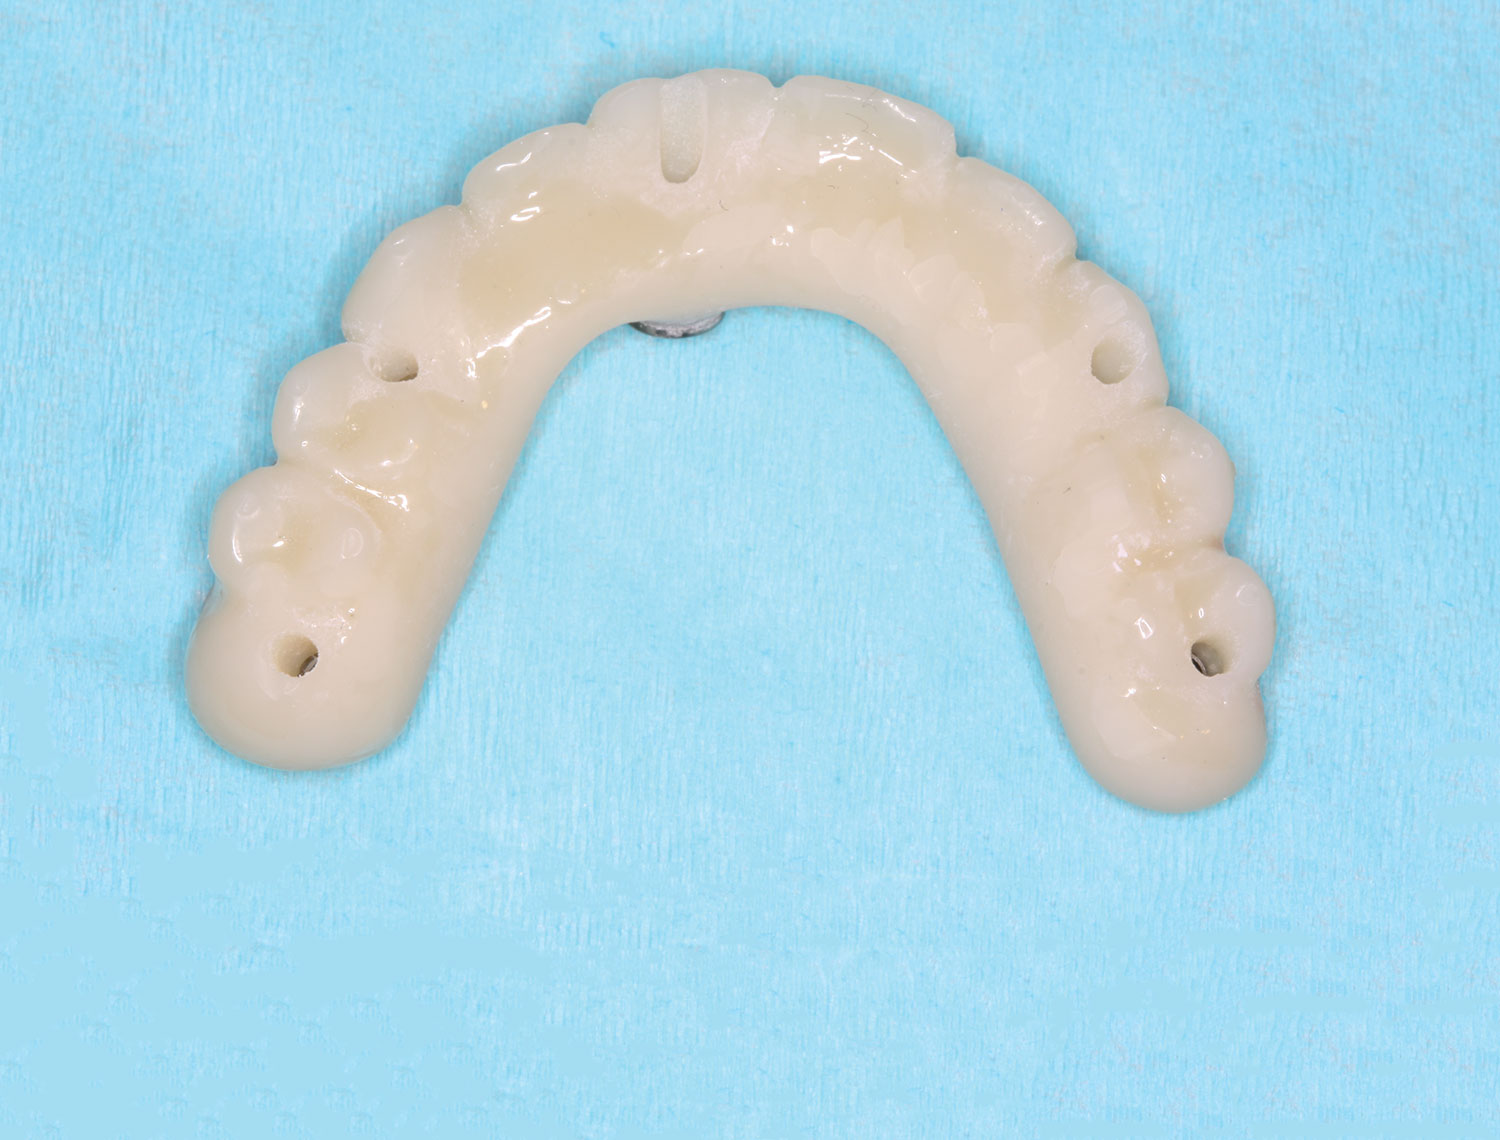

Fig 31. Mandibular provisional prosthesis printed demonstrating screw-access holes in prosthetically correct positions.

Figure 31

This file was then electronically returned to the dental team via the proprietary web portal. The office staff then sent the STL design file to the practice's 3D printer software, and the appropriate color nanoceramic resin was used to print the prosthesis at 100 microns. Once this was accomplished, the prosthesis was stained and glazed and gingival color was applied to establish optimum esthetics.

The completed prosthesis was then screwed directly onto the multi-unit abutments with Rosen screws with no ti-bases and torqued to 20 Ncm. Screw-access holes were filled, and no occlusal adjustment was necessary. The fit of the prosthesis was precise and stable and the phonetics of the patient was ideal. The patient was overwhelmed by the significant esthetic improvement with this set of teeth in place.